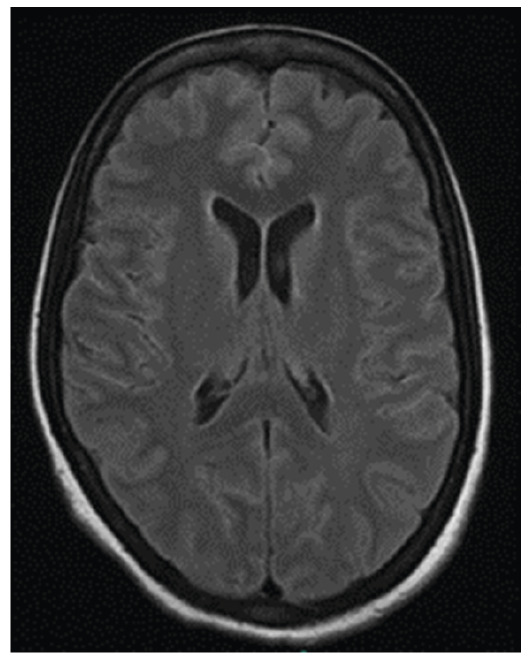

Cryptococcal disease is the third most common invasive fungal infection in solid organ transplant recipients and is associated with high-morbidity and -mortality rates. Donor-derived Cryptococcus spp. infection typically manifests within the first month post-procedure and has historically been caused by C. neoformans complex, predominantly in kidney recipients, but also after liver transplantation. We report the first documented case of donor-derived, early-onset C. gattii complex meningoencephalitis following liver transplantation in a 54-year-old woman, successfully treated with amphotericin B and fluconazole, and review the relevant literature.